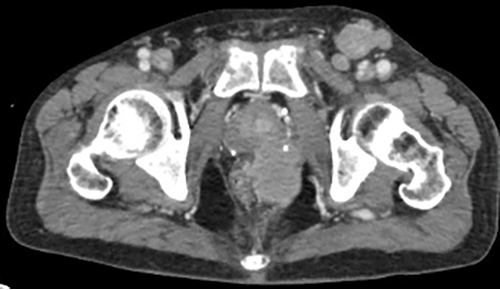

A positron emission tomography-computed tomography (PET-CT) scan was performed, demonstrating the left perianal mass predominantly occupying the ischiorectal fossa with a loss of the normal fat plane between the seminal vesicles and the rectal wall, suggesting local invasion (Figure 3). PET-CT was also significant for multiple enlarged pelvic and inguinal lymph nodes bilaterally, multiple hypermetabolic nodal stations below the diaphragm, and areas of extra nodal disease in the bone marrow and spleen, consistent with Ann Arbor stage IV disease.

Figure 3: CT I mages of Perianal Mass. Published With Permission

Hyperdense mass in left ischiorectal fossa, extending into left supralevator space

Left external iliac lymphadenopathy. Cranial extent of tumor with mass effect on rectum